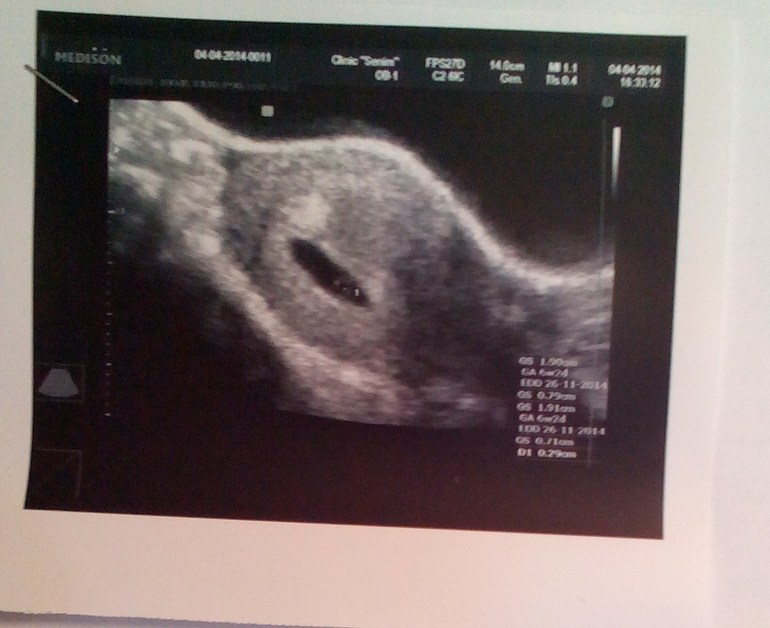

Маленький,но ЕСТЬ.....!!!!!!!!!

Помогите, под скажите, расскажите.....А,то я совсем не Бум -Бум...Норма ли это......И как часто они ставят эту УГРОЗУ..........